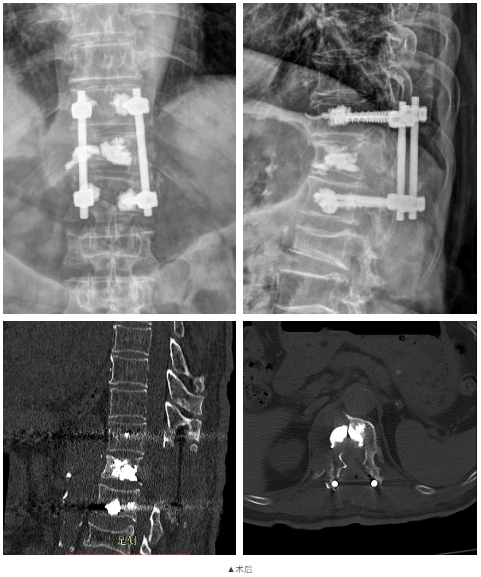

手术当日,姜树东会同脊柱外科(骨四科)主治医师梁得华在全麻下为患者进行后路胸椎椎板切除椎管减压、T12椎体强化术、T11、L1椎弓根钉内固定术、植骨融合术。手术过程顺利。术后患者恢复良好,腰背部显著缓解,在支具保护下可以进行常规活动。患者在术后1周顺利出院,后续接受抗肿瘤相关治疗。